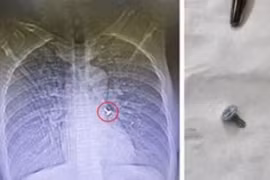

Cứu bé nuốt cây đinh vít, sơ cứu dị vật đường thở thế nào?

Các bác sĩ khoa Tai Mũi Họng đã nội soi đường thở cho bệnh nhân và gắp ra 1 chiếc đinh vít bằng sắt sắc nhọn từ phổi trái của bệnh nhân.